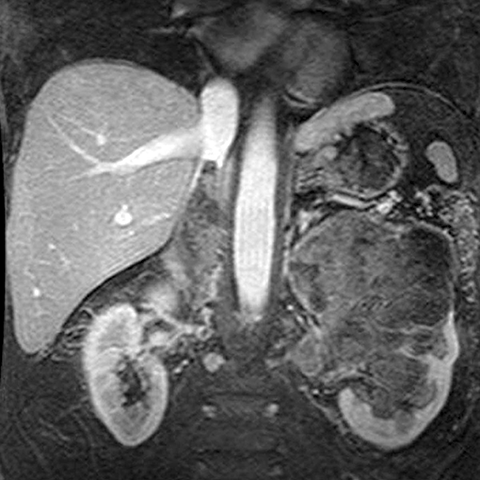

67-year-old male with flank mass and hematuria [1 of 3]